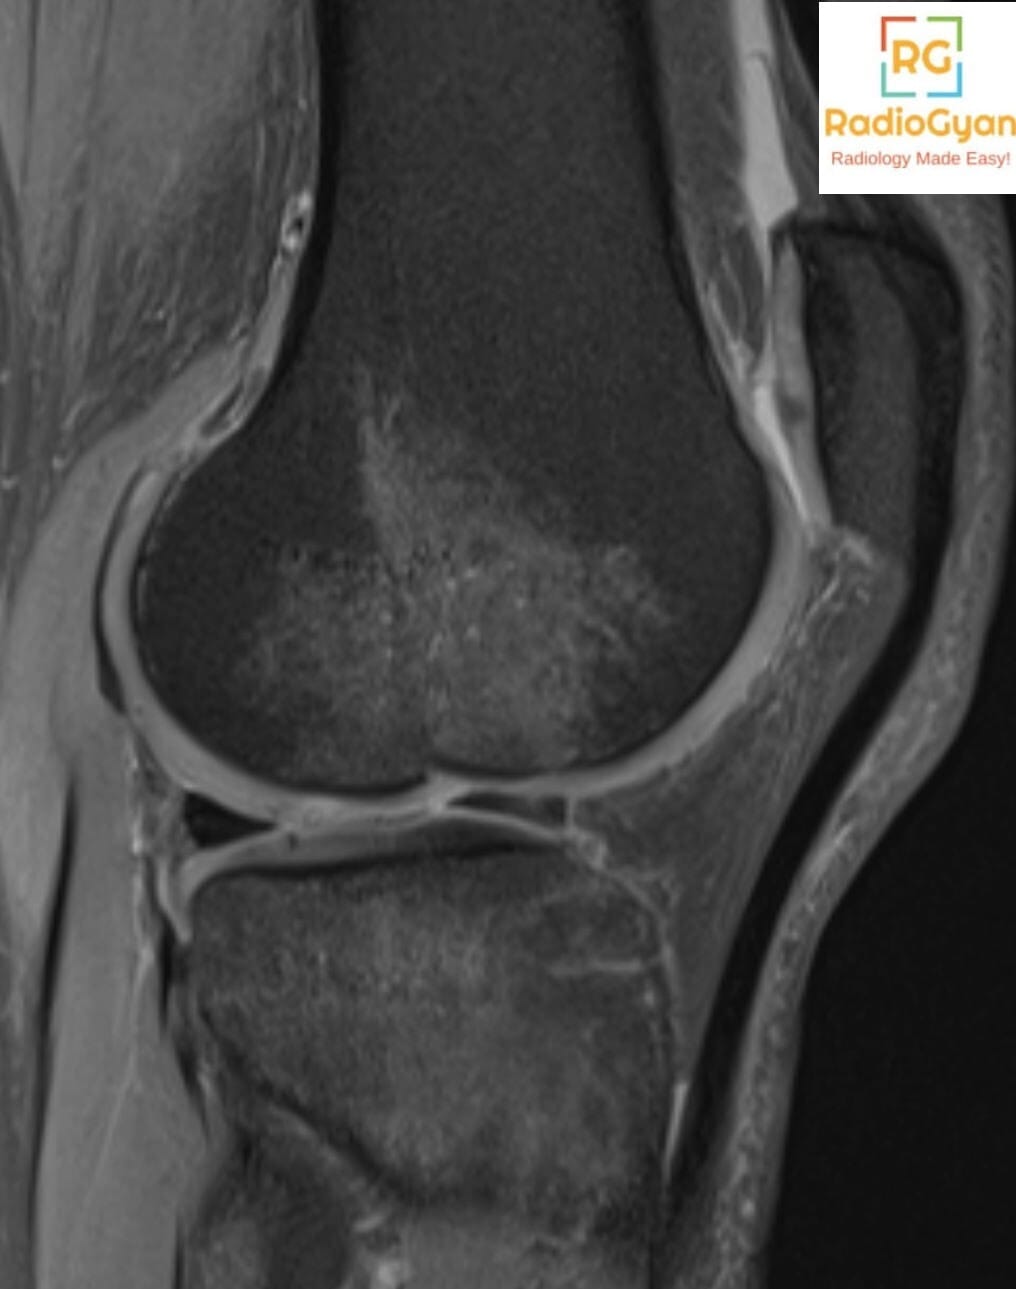

The lateral femoral notch sign is caused by an osteochondral impaction fracture of the lateral femoral condyle typically associated with acute or chronic anterior cruciate ligament (ACL) tears. This sign reflects a bone depression or notch on the lateral femoral condyle resulting from impaction trauma during the injury that causes ACL rupture. It is commonly found in patients with ACL tears and indicates significant bone contusion or fracture of the lateral femoral condyle. Clinically, it is associated with knee instability and ligamentous injury.

It is called the “lateral femoral notch sign” because the abnormal finding is a notch or depression on the lateral femoral condyle seen on lateral knee radiographs or MRI. The term describes the visual appearance of an unusually deep notch in the bone contour of the lateral femoral condyle.

This sign develops because during an ACL tear, the lateral femoral condyle impacts against the lateral tibial plateau forcefully, causing an osteochondral impression fracture. The resulting bone depression increases the depth of the normal lateral condylopatellar sulcus (lateral femoral notch). This bone contusion and impaction fracture deepen the notch beyond physiologic limits, which can be measured on imaging. The lateral femoral notch sign serves as an indirect indicator of the underlying ligamentous injury and knee instability caused by ACL rupture.